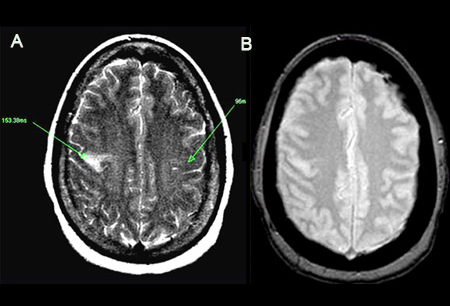

[Figure caption and citation for the preceding image starts]: (A) T2-შეწონილი სურათი გვიჩვენებს გაძლიერებულ სიგნალს, რომელიც წარმოადგენს პროლონგირებულ T2-ს. წარმოაჩენს პათოლოგიურ T2-ს 153.38 მწმ მარცხნივ, შედარებით ნორმალურ კონტრალატერალურ მხარესთან (96 მწმ). მიაქციეთ ყურადღება, რომ დაზიანების კერა განლაგებულია აღმავალ ფრონტალურ ხვეულზე. (B) ექო გრადიენტული სურათი ავლენს ჰემოსიდერინის ნაერთებს რკინის მაგნიტის მგრძნობელობის გამო. უარყოფითი შედეგის შემთხვევაშიერიკ ე. სმიტის პერსონალური კოლექციიდან; გამოიყენება ნებართვით [Citation ends].